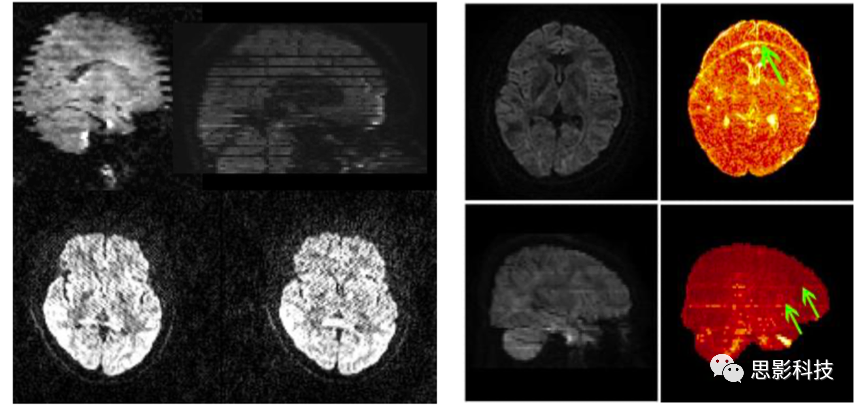

圖例:不同偽影示意圖

掃描參數檢查,包括TR、體素大小、掃描時長等參數,確保參數合適與統一;圖像偽跡檢查,包括鬼影、變形等;其他檢查,包括頭動狀況、圖像是否缺損等。對于可能發(fā)現的數據質量問題,思影將提供合適的參考意見。也可幫助客戶進行掃描參數的設計。